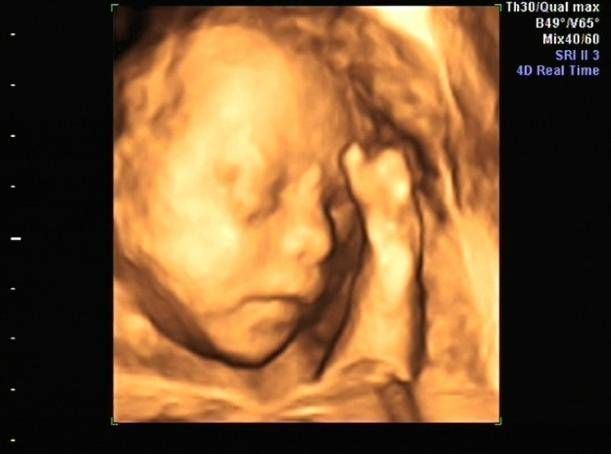

孕期产检,相信不少孕妈妈都很期待四维排畸这一项了,四维彩超排畸检查有不少准妈妈也想带着准爸爸进去,一同分享这其中的喜悦。

【为什么有些医院做四维彩超不让家属陪同这些原因,大家有权知道】小茹怀孕24周左右的时候,身边朋友提醒她这个时候需要做四维大排畸了,不仅能知道胎宝宝发育状况,还可以提前看到宝宝的长相。